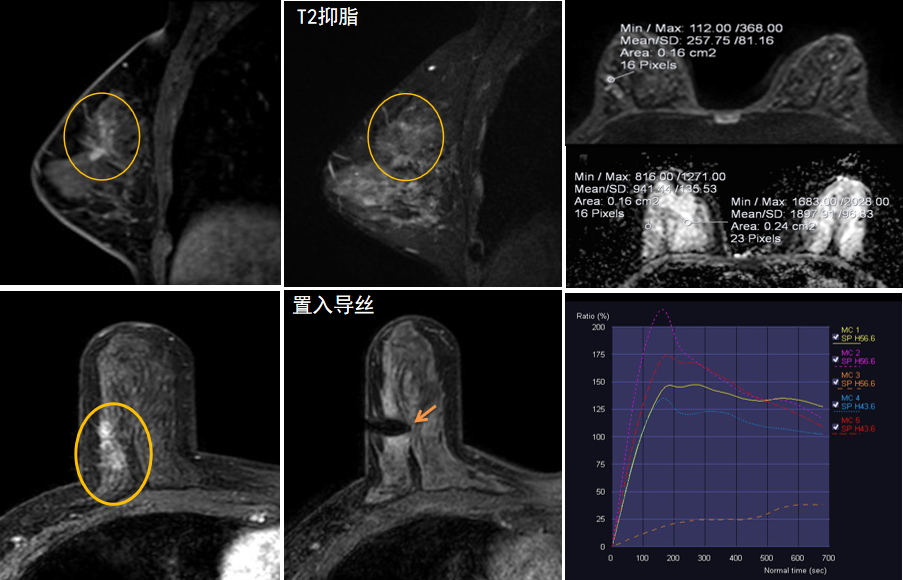

今年45歲的某女士,兩個(gè)月前行超聲檢查發(fā)現(xiàn)右乳結(jié)節(jié),乳腺X線攝影檢查提示右乳外上象限局部腺體結(jié)構(gòu)扭曲并簇狀無(wú)定形鈣化,為了進(jìn)一步評(píng)估病變性質(zhì)并確定范圍進(jìn)行了乳腺M(fèi)R平掃 DWI 增強(qiáng)的檢查,經(jīng)MR評(píng)估發(fā)現(xiàn)右乳病變范圍較廣,評(píng)估為BI-RADS 4類(lèi)可疑病變,需要取得病理學(xué)結(jié)果。

陳寶瑩主任及其帶領(lǐng)的MR介入診療小組詳細(xì)詢問(wèn)了病情,分析了患者資料,并與患者和臨床醫(yī)生進(jìn)行了充分溝通,確定于手術(shù)前為患者實(shí)施MR引導(dǎo)下的病變穿刺導(dǎo)絲定位和體表范圍確定。手術(shù)前陳寶瑩主任帶領(lǐng)聶品醫(yī)師、馬小偉技師、韓愛(ài)萍護(hù)士長(zhǎng)等MR介入診療小組成員,借助MR高清的圖像顯示和定位系統(tǒng),確定病變范圍,精準(zhǔn)穿刺置入定位導(dǎo)絲,并準(zhǔn)確標(biāo)記出病變體表范圍,整個(gè)過(guò)程患者無(wú)任何不適。在定位導(dǎo)絲和體表范圍標(biāo)記的輔助下,甲乳外科劉曉敏主任精準(zhǔn)切除了病變,解除了患者的后顧之憂。

國(guó)內(nèi)外指南均建議40歲以上的女性每年行一次雙乳X線攝影(鉬靶)檢查,以篩查乳腺癌。對(duì)于乳腺癌高危人群40歲以前即建議開(kāi)始乳腺癌篩查,除了進(jìn)行乳腺X線攝影(鉬靶)篩查外需要補(bǔ)充MR檢查,MR檢查敏感性最高,能夠發(fā)現(xiàn)大量X線攝影和超聲檢查陰性的可疑病變,基于多模態(tài)、多參數(shù)的結(jié)構(gòu)和功能成像的基礎(chǔ)上,MR能夠精準(zhǔn)顯示病變位置、范圍以及病變內(nèi)的活性區(qū)域,MR引導(dǎo)下的介入診療不但解決了僅在MR顯示的病變的處置難題,而且能夠精準(zhǔn)定位活性區(qū)域,保證了定位、活檢及旋切的準(zhǔn)確性。